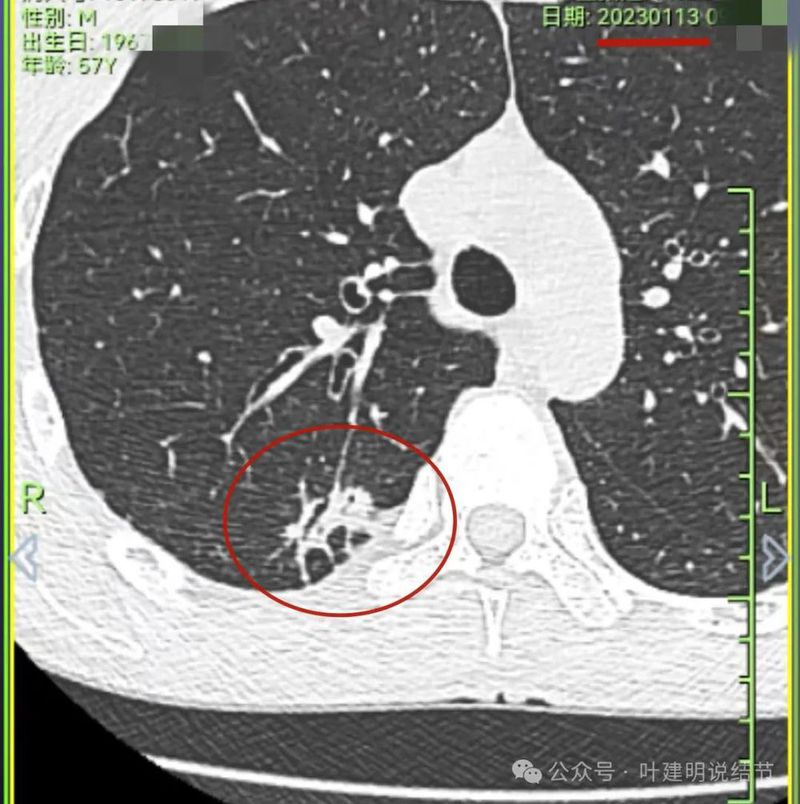

上图是2023年1月时的,虽也基本上实性,但明显病灶相对较小,而且膨胀感不太明显些。